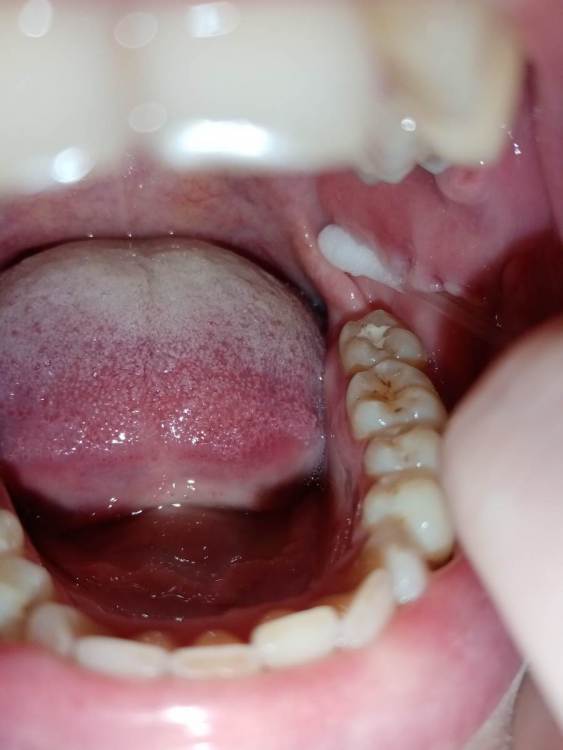

СмирноваД Опубликовано 29 июня, 2023 Поделиться Опубликовано 29 июня, 2023 Уважаемые стоматологи. Прошу Вашей помощи в поиске проблемы. Зуб удалили 2 года назад, но покоя там слизистая не дает. Болит, Разговаривать не дает вообще. Как буд-то там все пришили, и щеку и тяж со стороны горла. Какая-то шишка растет в конце верхней челюсти и как-будто давит там. Срослось оно вот таким образом "V"(со слов врача). Дергает щеку сильно , как-будто она прям пытается оторваться оттуда. и при наклоне головы прям в это место отдает. Со стороны горла тяж пришитый прям лоскутом к челюсти со стороны языка, трется об язык и тянет так сильно, что не дает разговаривать вообще, больно любые напряжения(разговаривать, глотать, пить,смеяться, и т.д.) прям чувствую как оно там все двигается, как нахождении чего-то инородного. Постоянно там все полощу, держу воду, потому что жжёт сильно. И доходит до рвотного рефлекса. Со стороны щеки,за зубом 4.7 корман. Пища попадает , и вытащить ее проблематично. Постоянно ощущение воспаления и лазию туда языком отодвигаю этот тяж, засовываю туда ватный диск, что бы просто снять напряжение и в этот момент могут быть такие жутки спазмы, что замираешь от боли. До трясучки и панических атак уже. Прикусываю там все, при чом даже с шиной (сплинт), щека лезет между зубов, приходится щеку вытаскивать.Шину ношу уже 10 месяцев, а толку нет. Рефлекторно, стараешься не двигать просто правой стороной вообще. Гнатолог , который делал шину, сказал, что нужно убирать рубцы, они все тянут. Но когда дошло дело до хирурга, хирург развел руками и сказал жить так, т.к. он ни чего сделать не может. Мало того у меня проблемы с суставом. а из-за этого напряжения на столько хуже, что к вечеру ни то что бы разговаривать, я и глотать слюну не могу. Сустав у меня теперь болит постоянно от напряжения, жуткие спазмы по всей голове, челюсти, до горла болит, с переходом на шею. При чом все врачи видят эти рубцы, что все прикусываю, трогают и мне больно, но говорят все по разному : один- надо искать, другой - там воспаление, третий- прикус, четвертый -как вы себе представляете это, это нужно было убирать сразу, пятый-сустав. Просто как идти к ортодонту с такими болями? И так же искала врача по пластике, но безрезультатно. На кт и снимках нет ни чего. Помогите, пожалуйста, хоть как-то разобраться. 230310_183333.rar Ссылка на комментарий

Bier Опубликовано 16 августа, 2023 Поделиться Опубликовано 16 августа, 2023 я вижу рубец на щеке, вы накусали его, ну если он мешает можно его отрезать. Но по источнику боли соглашусь с Анной. Ссылка на комментарий